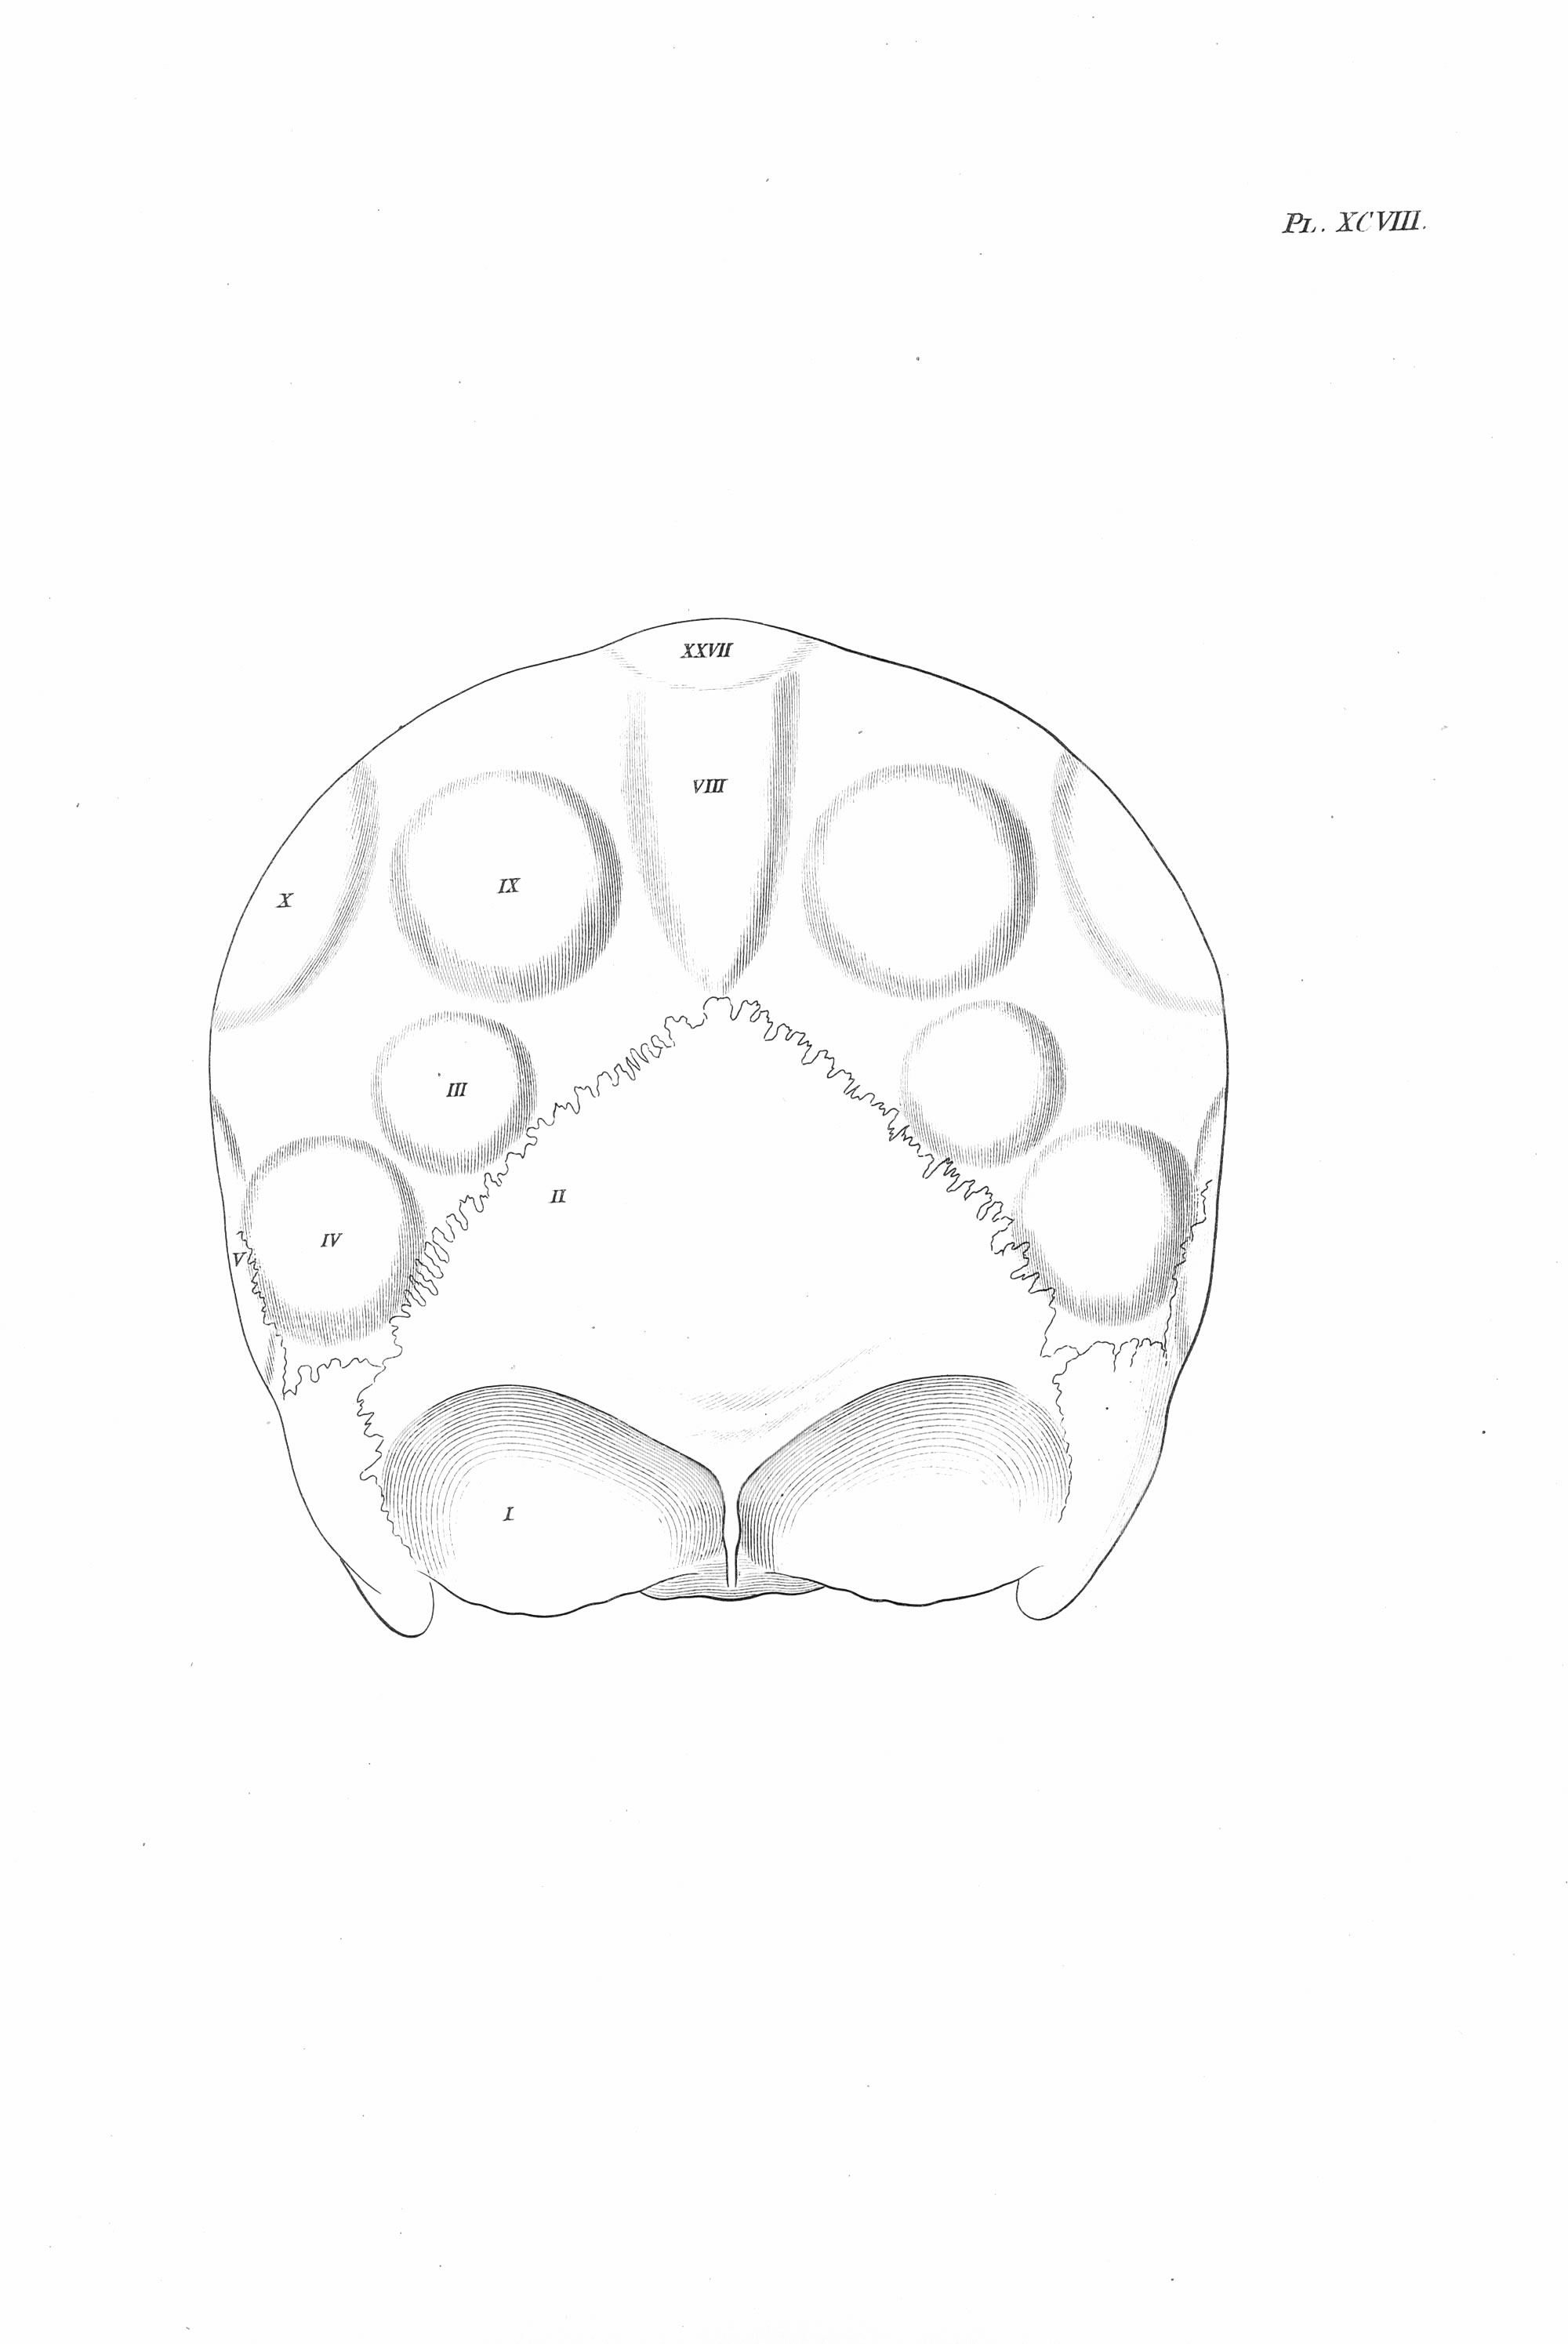

Gall, F. J. (1818). Anatomie et physiologie du système nerveux en général, et du cerveau en particulier, Avec des observations sur la possibilité de reconnoître plusieurs dispositions intellectuelles et morales de l´homme et des animaux, par la configuration de leurs têtes.

Librairie Grecque-Latine-Allemande, Vol. 3, I-XXXV u. 1-379 100 planches.